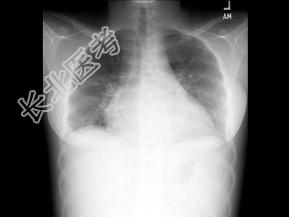

- 单项选择题女,17岁, 背部和正中胸部急性疼痛和带状疱疹感染,结合图像, 最可能的诊断是 ( )